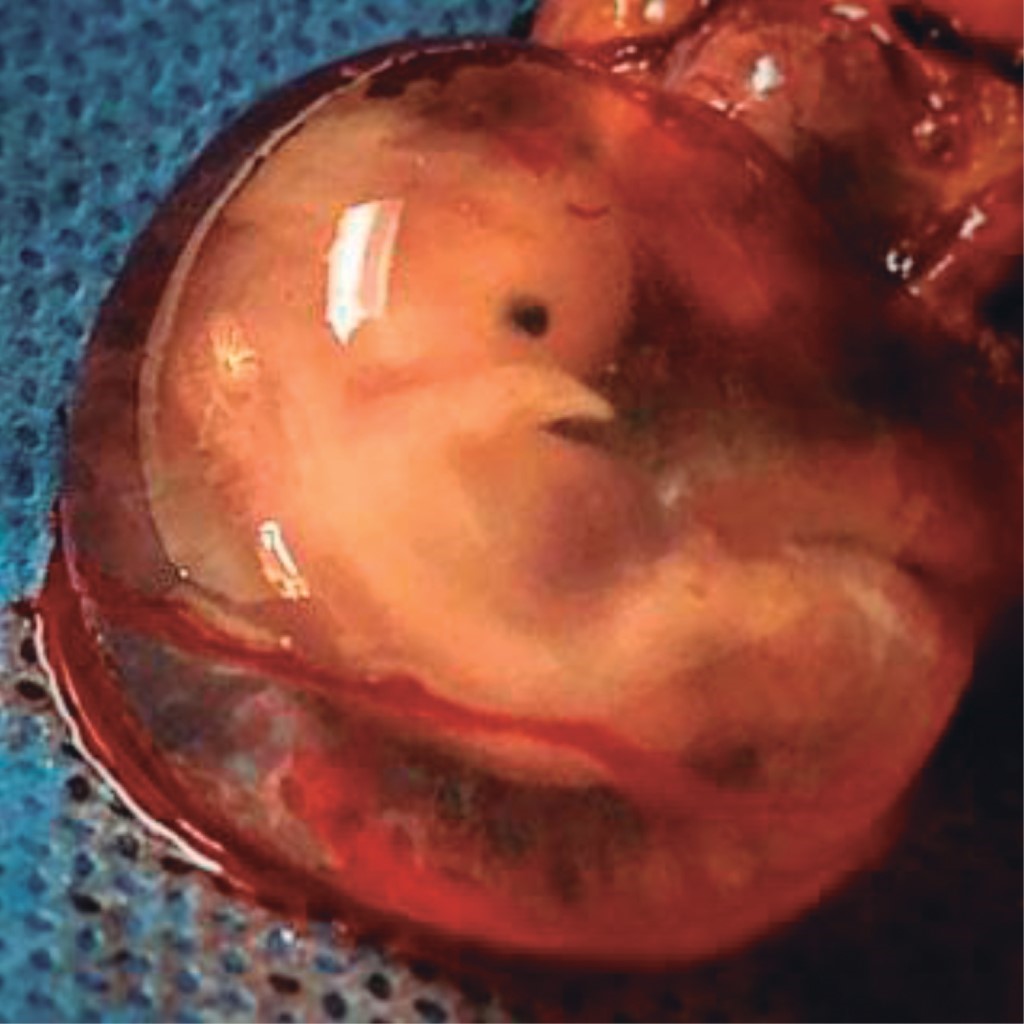

Photography Contest. Commemorative Congress for the XX Anniversary of the Maternal and Child Institute of the State of Mexico

Figure 1

Figure 2

Figure 3

Figure 4

Figure 5